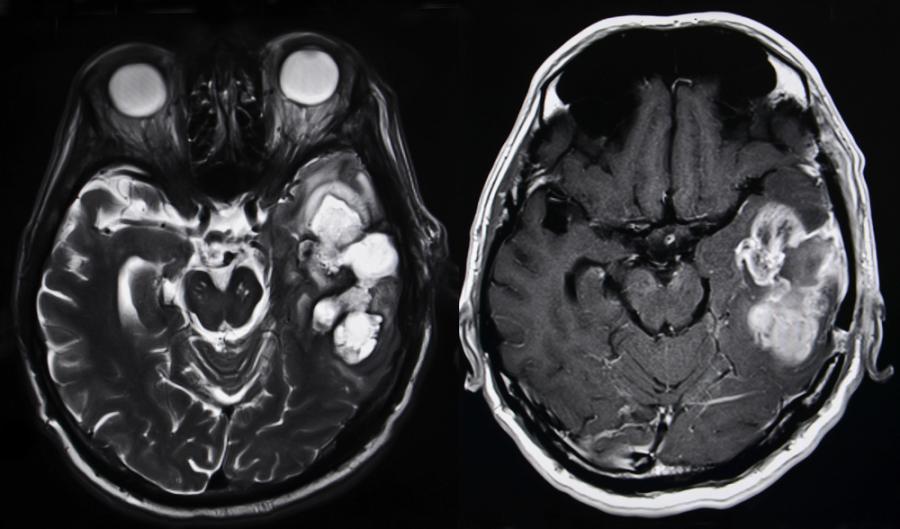

Често ранното диагностициране на туморите на мозъка е доста трудно, отчасти защото повечето хора се подлагат на компютърна томография или магнитно-резонансна томография едва при появата на първите неврологични проблеми – например обездвижване на крайници, неспособност да говорят и т.н. Когато туморите бъдат открити посредством тези методи, те вече са пораснали до такава степен, че не могат да бъдат отстранени изцяло, а това от своя страна намалява шансовете за оцеляване. Ето защо лекарите се нуждая от точни, лесни и евтини методи за ранно диагностициране на туморите на мозъка.